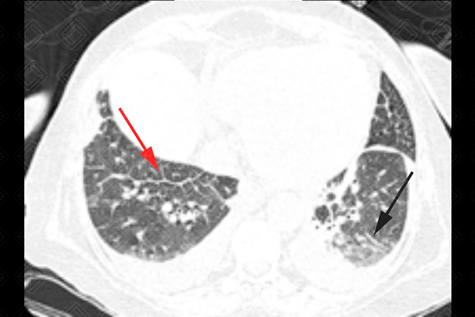

Texto alternativo para a imagem Figura 1. Créditos: Dra. Elazir Mota - Rio de Janeiro/RJ

Descrição das figuras 1, 2 e 3: Tomografia computadorizada de tórax. Espessamento liso dos septos interlobulares (setas vermelhas) associado a discretas áreas em vidro fosco na base pulmonar esquerda (seta preta), moderado derrame pleural bilateral (asterisco azul), derrame pericárdico (asterisco amarelo) e cardiomegalia. O conjunto de achados é sugestivo de congestão pulmonar.

• Tomografia computadorizada de tórax: Opacidades em vidro fosco, espessamento dos septos interlobulares, espessamento peribroncovascular, pavimentação em mosaico, aumento do calibre vascular, consolidações e nódulos de espaço aéreo (como nas figuras acima).